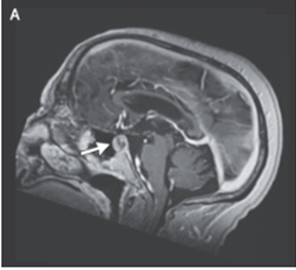

81歳男性。既往として機能不全性下垂体巨大腺腫があり、画像フォローにて経過観察されている(A)。

頭部MRIではT1強調像にて出血を伴う下垂体病変の拡大が明らかになった。